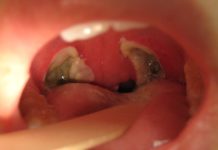

What Is a Tonsillectomy?

The tonsils may be removed due to repeated infections or enlargement that affects breathing.A tonsillectomy is surgery t